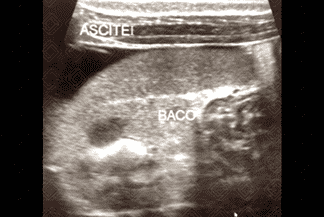

Texto alternativo para a imagem Figura 2. Créditos: Dra. Elazir Mota - Rio de Janeiro/RJ

Descrição da lesão: Atresia de vias biliares. Ultrassonografia do abdome evidenciando vesícula "atrésica" (eixo longitudinal < 15 mm e com contornos irregulares) (figuras 1 e 2), cordão hiperecogênico anterior à bifurcação da veia porta (figura 3), esplenomegalia e ascite (figura 4).

• Alteração na morfologia da vesícula biliar (VB): 1. Presença ou ausência de VB; 2. Dimensões da VB (diâmetro no eixo longitudinal inferior a 15 mm sugere VB atrésica, se > 15 mm é necessário avaliar sua morfologia); 3. Morfologia da VB (contorno regular ou irregular, presença ou ausência da mucosa regular hiperecogênica em toda extensão da VB);